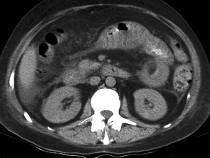

问题 男,32岁,阵发性腹痛、腹胀,伴恶心、呕吐,腹部可触及包块,影像检查如图,最佳的诊断是什么 ( )

选项 A.小肠肿瘤 B.麻痹性肠梗阻 C.空肠套叠 D.回肠套叠 E.结肠套叠

答案 C